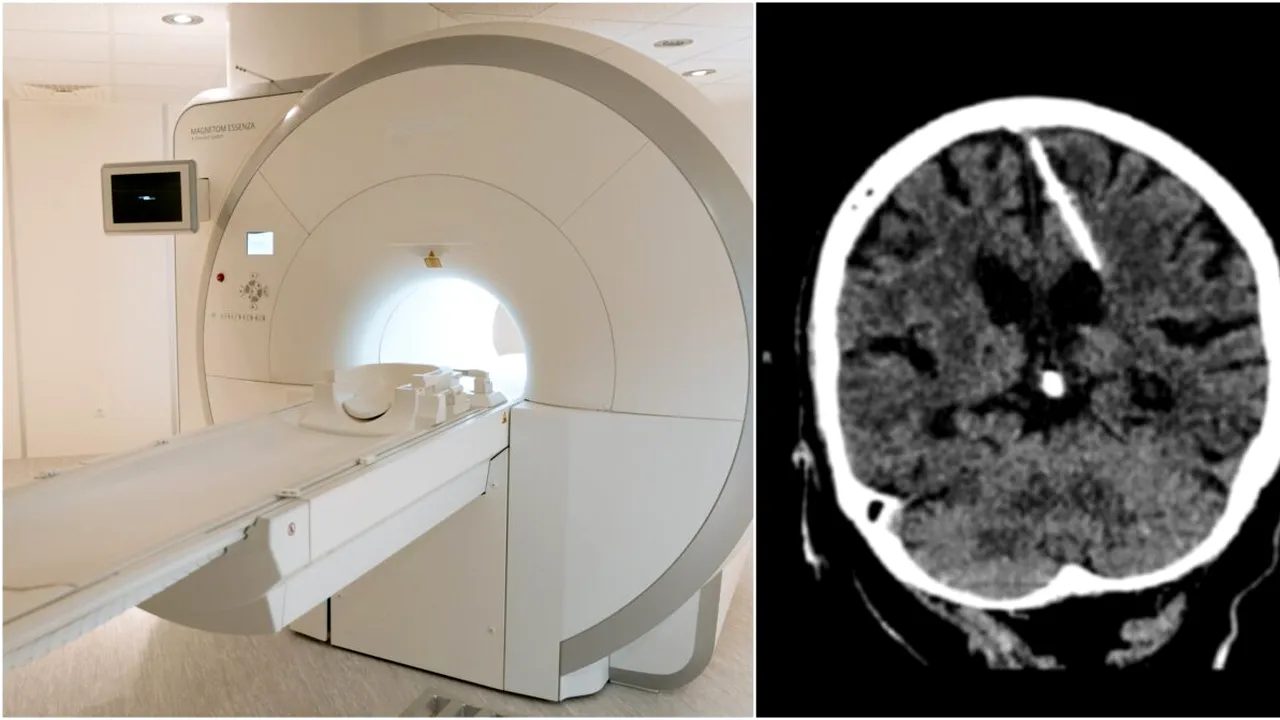

Femeia locuiește în Rusia, iar medicii au făcut descoperirea șocantă în timpul unei tomografii. Timp de 80 de ani, nimeni nu a știut ce era în capul femeii: un ac de 3 centimetri.

Ministerul Sănătăţii din Rusia a postat imaginile tomografiei pe contul de Telegram şi a precizat că investigaţiile medicale au fost făcute în acest an, fără a da însă o dată exactă. Acul a fost descoperit în lobul parietal stâng al creierului, iar medicii cred că părinţii femeii au încercat să o omoare la naştere, potrivit Insider.

Medicii  nu vor încerca să îndepărteze obiectul din capul femeii deoarece această procedură i-ar putea pune serios viaţa în pericol.

Experţii Ministerului rus al Sănătăţii spun că această practică era una destul de comună în timpul celui de-al Doilea Război Mondial. Părinţii ajungeau într-o situaţie într-atât de disperată încât încercau să-şi omoare nou-născuţii pentru a nu fi expuşi la ororile războiului. Cea mai la îndemână metodă era înfigerea unui ac într-o zonă moale a capului copilului, acolo unde oasele craniului nu erau complet dezvoltate.